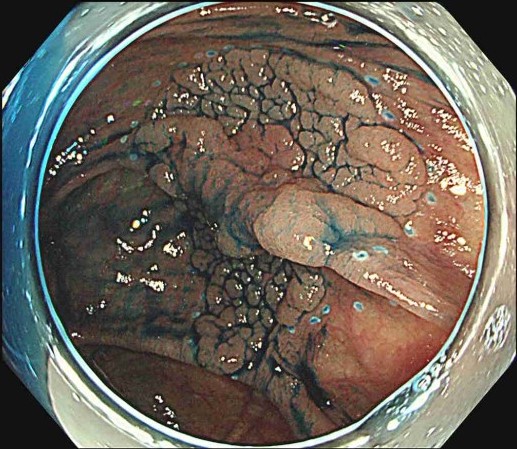

EMR(内視鏡的粘膜切除術)

- ポリープの下に生理食塩水などを注入し、スネア(輪っか)で切除する

- 比較的シンプルな方法

ESDの手順

Figures adapted from: Nagata M. Endoscopy 2024; 56: E699–E700.

Licensed under CC BY 4.0 (https://creativecommons.org/licenses/by/4.0/)